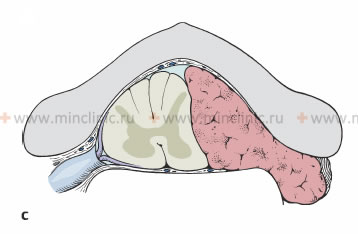

ხერხემლის არხის სიმსივნეები იყოფიან პირველად და მეორეულ (მეტასტაზები) სიმსივნეებად. ეს სიმსივნეები შეიძლება ლოკალიზებული იყოს ზურგის ტვინის მყარი გარსის ზევით (ექსტრადურალური ან ეპიდურალური) ან ქვევით (ინტრადურალური). გარსქვეშა (ინტრადურალური) სიმსივნეები შეიძლება განლაგებული იყოს ზურგის ტვინის პარენქიმის გარეთ ან შიგნით (ექსტრამედულარული, ინტრამედულარული).

ინტრადურალური ექსტრამედულარული სიმსივნით ზურგის ტვინის დაზიანების დასაწყისში ავადმყოფებს უვლინდებათ მგრძნობელობის ფესვური დარღვევა და ასიმეტრიული ნევროლოგიური დარღვევების სინდრომი. ზურგის ტვინის კომპიუტერული ტომოგრაფიისა და მიელოგრაფიის დროს ვლინდება ზურგის ტვინის სუბარაქნოიდულ სივრცეში მდებარე სიმსივნის საწინააღმდეგო მხარეს ზურგის ტვინის გადაადგილების (დისლოკაციის) ტიპური სურათი.